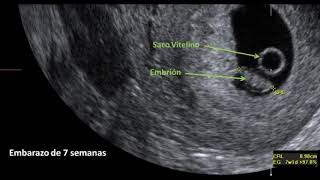

Si Hay Vesicula Vitelina Es Buena Señal, 🤷♀️Cómo es un #embarazo no evolutivo: 4 señales⭐ ✅Dr. Felix Lugo 🥇😀, 9.43 MB, 06:52, 454,090, MIGINEBLOG, 2019-09-21T10:59:07.000000Z, 3, Bañera subterraneo estoy sediento si hay vesicula vitelina es buena, mappingmemories.ca, 1280 x 720, jpeg, WebSi se ve la vesícula vitelina en un 90%luego se ve el embrión.al fin y al cabo es la que esta alimentando al embrioncito.mucho ánimo hola yo me hice la primera ecografia a las 5 semanas y no se veia el embrión pero si la vesicula vitelina lo que es. WebSi Hay saco vitelino .. ¿es buena señal?: Segun mi FUM estaria de 10 semanas justo .. segun ecografia estoy de 6.3 semanas ... solo se vio saco gestacional. WebAsí como la placenta, la vesícula vitelina da soporte de oxígeno, nutrientes y sangre al embrión, pero con una diferencia, es temporal hasta que la placenta logra alcanzar. WebSi hay vesícula vitelina es buena señal 6 semanas de embarazo con saco gestacional y vesicula vitelina - Foro embarazo Saco gestacional normal y vesicula., 20, si-hay-vesicula-vitelina-es-buena-senal, Novedades y Muebles WebSi se ve la vesícula vitelina en un 90%luego se ve el embrión.al fin y al cabo es la que esta alimentando al embrioncito.mucho ánimo hola yo me hice la primera ecografia a las 5 semanas y no se veia el embrión pero si la vesicula vitelina lo que es. WebSi Hay saco vitelino .. ¿es buena señal?: Segun mi FUM estaria de 10 semanas justo .. segun ecografia estoy de 6.3 semanas ... solo se vio saco gestacional. WebAsí como la placenta, la vesícula vitelina da soporte de oxígeno, nutrientes y sangre al embrión, pero con una diferencia, es temporal hasta que la placenta logra alcanzar. WebSi hay vesícula vitelina es buena señal 6 semanas de embarazo con saco gestacional y vesicula vitelina - Foro embarazo Saco gestacional normal y vesicula.

WebLa vesícula efectivamente comprueba que hay o hubo embrión, repite la ecografía, sino hay embrión hubo una perdida. Saludos y gracias por escribir. Dra. Marlene. WebSi hay vesícula vitelina es buena señal - Foro embarazo. Efectos secundarios de la operación de vesícula biliar - Foro salud. Puedo dormir de lado después de una.

WebVesícula vitelina pequeña. Puede ser un indicativo próximo de aborto. Una vesícula vitelina pequeña puede verse muy al principio del embarazo o bien, a partir de. WebEl saco vitelino es la primera estructura de origen embrionario que puede ser visualizado en la ecografía, incluso antes del feto. También se le puede denominar vesícula vitelina y si. WebColombella 17/03/13. estoy preocupada pq aun no pudimos ver el embrion en la semana 7+4 , solo s. gestacional y v. vitelina d 2.2mm. la beta en sangre siguio.